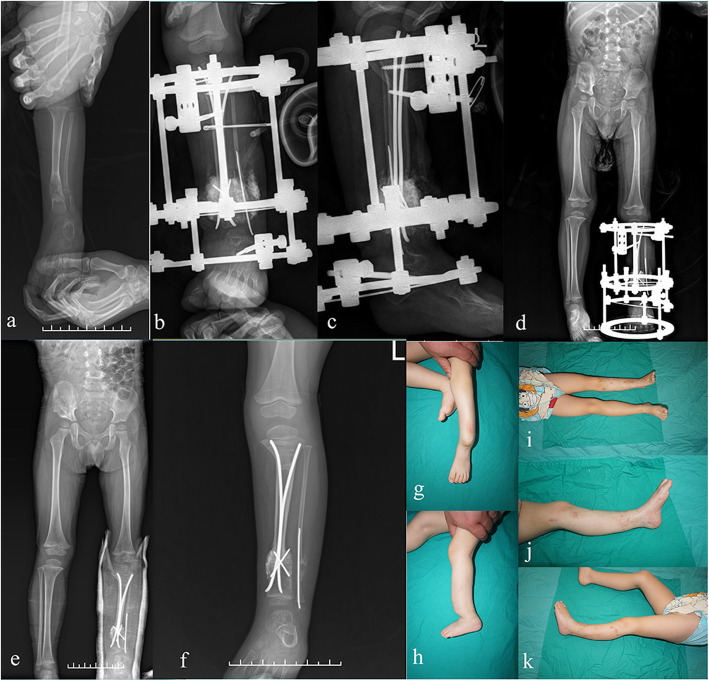

Fig. 3.

Case 12, a 2.5-year-old boy with CPT treated successfully with pseudarthrosis resection, the “Eiffel Tower” double TENs, bone grafting and external fixation. Pre-operative anteroposterior X-rays showing Crawford type III CPT with anterolateral bowing of tibia (a). Anteroposterior and lateral radiograph of the same patient taken immediately after combined surgery (b, c). X-ray taken 3 months post-operatively shows primary union of the pseudarthrosis site (d). Radiograph taken 6 months post-operatively shows a well-aligned and remodeled tibia without ankle valgus or tibia angulation (e). The nails were retained in the tibia medullary cavity with growth (f). Clinical appearance of the patient before (g, h) and after (i, j, k) the surgery. The patient had an AOFAS score of 82 and a 20 mm leg-length shortening at the finally follow-up